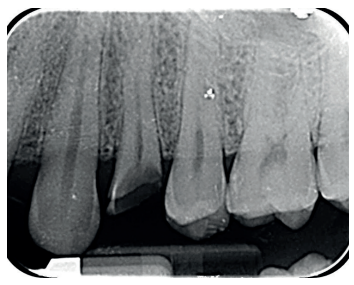

Las revisiones se realizaron de forma periódica hasta los 12 meses de seguimiento (Figuras 6 y 7), observando en todas ellas signos clínicos saludables. El paciente no presentó reabsorción radicular, anquilosis, ni problema periodontal en los exámenes radiográficos que se realizaron desde el diagnóstico hasta el año (Figuras 8 -12); y la ganancia de ferrule obtenida de 2mm se mantuvo estable.

de seguimiento al año de la extrusión.

seguimiento al año de la extrusión.

momento de la endodoncia.

de las citas de seguimiento.